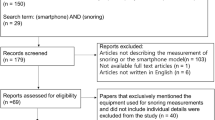

In total, 220 recordings from 11 patients were collected. We excluded recordings of <5 h (19 recordings) and finally included 201 recordings for further analysis. Three Asus ZenFone Max Plus (M1), three Apple iPhone 6, three Sony Xperia, one HTC One, and one Xiaomi Redmi 5 were used for the recordings. Short recordings (<5 h) were excluded because they might be reflective of patients with poor sleep or insufficient phone battery power. The patients’ basic demographic data are presented in Table 1. No patient had a history of diabetes, respiratory disease, sleep disorders, or alcohol or smoking problems.